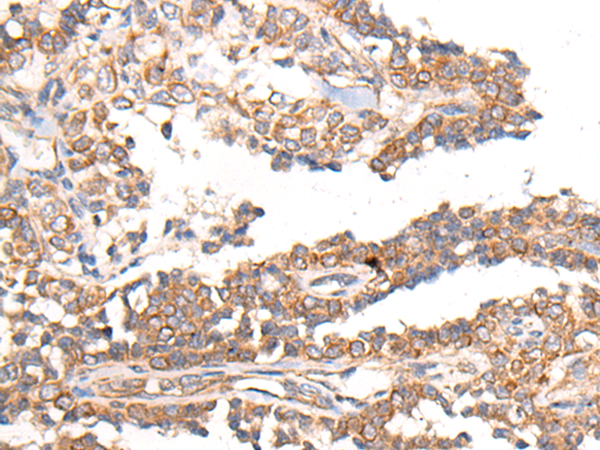

(The image on the left is immunohistochemistry of paraffin-embedded Human ovarian cancer tissue using 46617(MTNR1B Antibody) at dilution 1/55, on the right is treated with synthetic peptide. (Original magnification: x200))